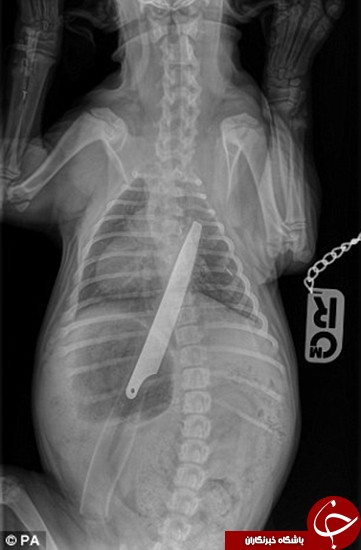

به گزارش زاهدانه به نقل از باشگاه خبرنگاران، میسی، سگی که 12 هفته بیشتر ندارد، بعد از خوردن و قورت دادن چاقو در حال ریکاوری در بیمارستان حیوانات است.

این سگ زمانی به بیمارستان حیوانات در گلاسگو برده شد که صاحب آن متوجه شد برای نفس کشیدن مشکل دارد و همین مسئله باعث شد تا او به سرعت میسی را به بخش اورژانس بیمارستان ببرد.

پس از معاینات انجام شده روی میسی، آن را به بخش عکسبرداری منتقل کردند و در اینجا بود که مشخص شد این سگ 12 هفته‌ای یک چاقوی 8 اینچی را قورت داده است که از معده و روده این سگ گذشته بود و برای او مشکل‌آفرین شده بود.

پزشکان به سرعت میسی را به اتاق عمل منتقل کردند و موفق شدند با عمل جراحی آن چاقو را که هنوز نوک آن در نای سگ گیر کرده بود، بیرون بکشند.